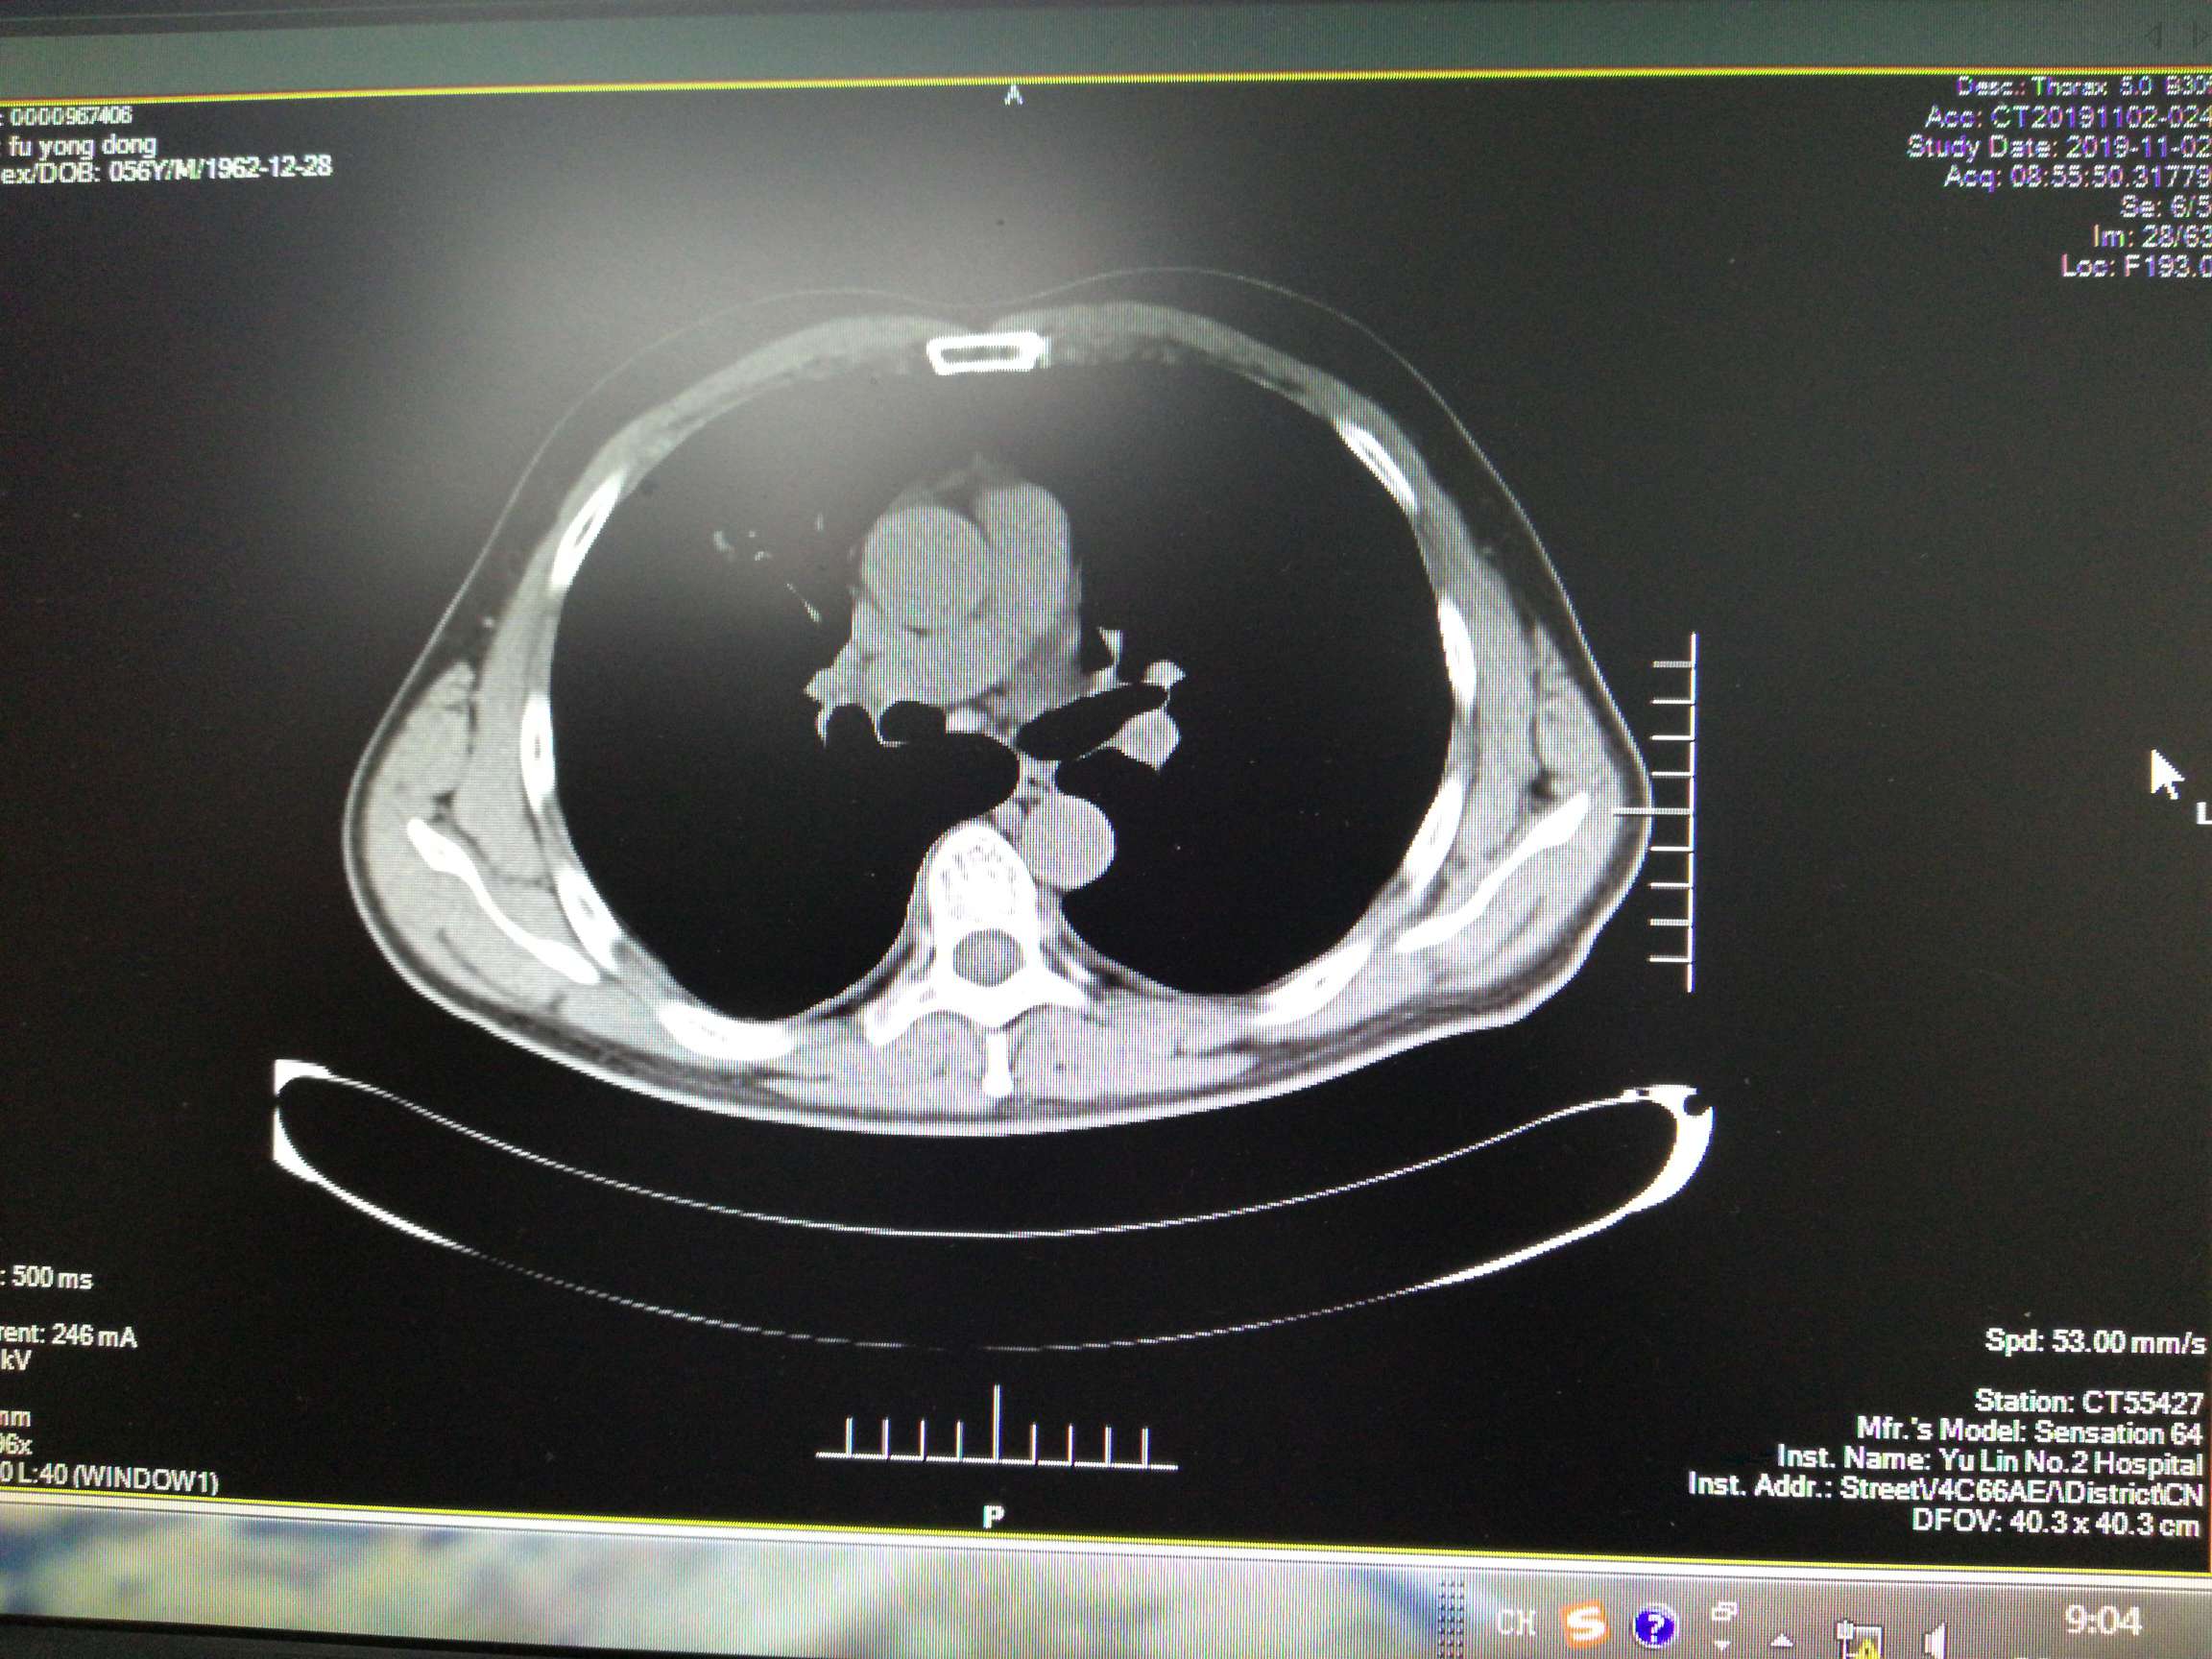

胸部右肺叶前段有3.4*6.7cm原发灶,右侧叶间裂、胸膜多处转移,纵膈内、右肺门旁、心隔角多处淋巴结转移,较大者1.3*1.0cm。有少量胸水。

期间病情迅速控制,原发灶从6. 7*3.4cm减小为1.7*1.5cm,头部从2.4*1.8cm减小到1.1*0.9cm,淋巴结较大者一直为1.3*1.0cm。胸水抽了两次,打了恩度,之后胸水没有再犯。肿瘤指标物一直减小。骨髓抑制严重。

10月份复查,cea继续缓慢上升,糖类125也开始上升。Ct显示原发灶从1.4*1.2cm增大到为2.7*1.4cm。pet-ct显示没有远端转移,头部转移灶失去活性,胸部原发SUVmax4.2,淋巴结SUVmax3.2。骨髓抑制现象继续持续,白细胞3.8,淋巴细胞百分比46.3%,中性细胞36.10%。在用K药之后再测白细胞3.2,可能骨髓抑制与K药有关。病人体感很好。总体判断为耐药迹象。